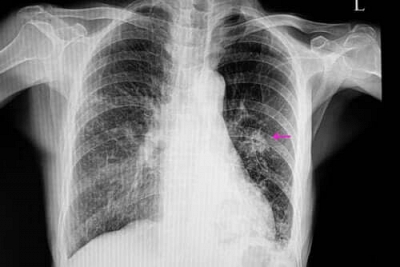

Nódulos pulmonares: quando fazer biópsia e acompanhamento

O achado de um nódulo pulmonar na tomografia ou radiografia assusta, mas…

Leia maisConheça os tipos e causas dos nódulos pulmonares e saiba quando este…